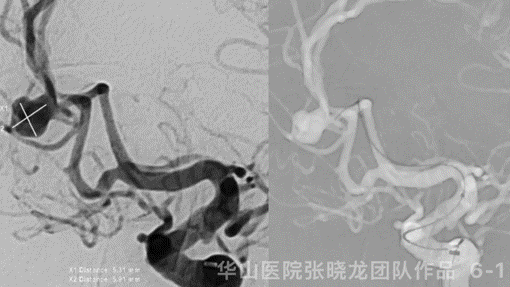

Figure 4 GIF. Rotational DSA confirmed a left A2/3 irregular aneurysm, a small anterior choroidal artery aneurysm and an ophthalmic aneurysm. The thick artery (arrow) was the left anterior choroidal artery instead of posterior communicating artery.